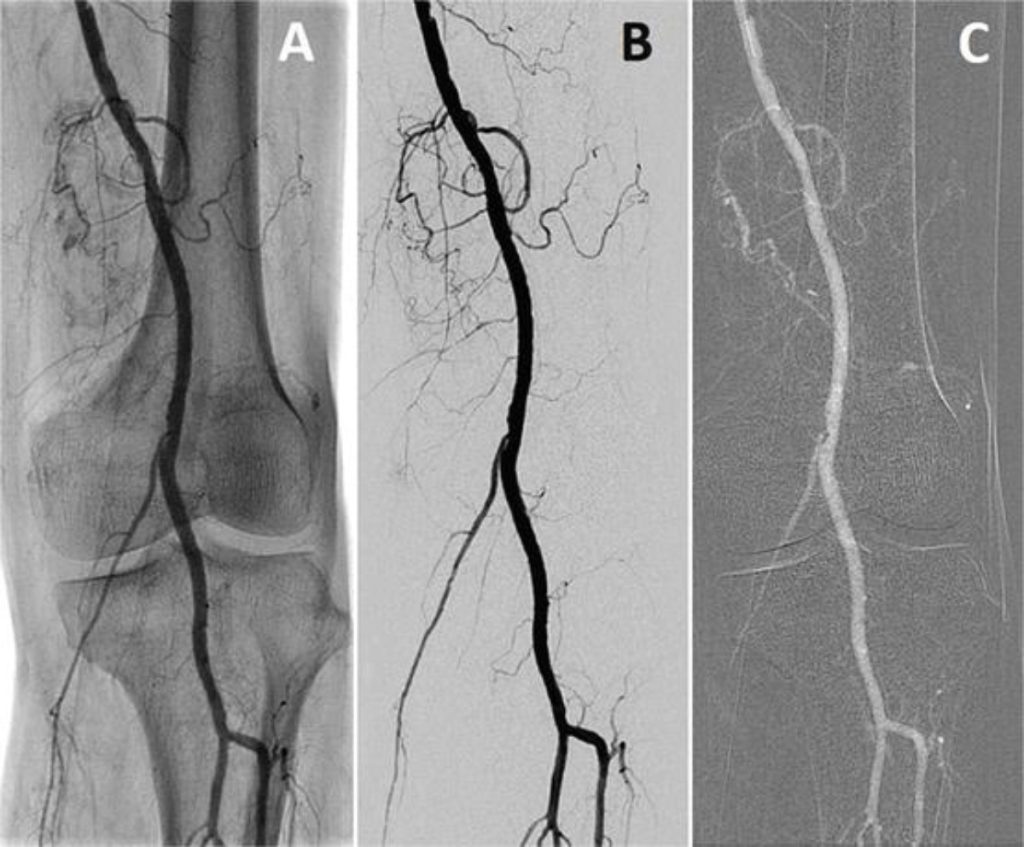

Η αθηροσκλήρωση, η οποία είναι γνωστή και ως αθηρωμάτωση ή αρτηριοσκλήρυνση, αποτελεί μια πάθηση που συναντάται πιο συχνά σε ανθρώπους μεγαλύτερης ηλικίας. Στο κείμενο που ακολουθεί θα μάθουμε τι είναι η πάθηση αυτή και η αθηρωματική πλάκα. Ακόμα, θα μιλήσουμε σχετικά με τα αίτια, τους παράγοντες κινδύνου και τα συμπτώματα της νόσου, στην ήπια και την πιο βαριά μορφή της. Τέλος, θα δούμε με ποιες εξετάσεις επιτυγχάνεται η διάγνωσή της, καθώς και πώς θεραπεύεται η αθηρωματική πλάκα.

Η αθηροσκλήρωση είναι μια χρόνια πάθηση κατά την οποία προκαλείται βλάβη στις μεγάλες και μεσαίου μεγέθους αρτηρίες, λόγω των λιπιδίων τα οποία υπάρχουν στα τοιχώματα των αρτηριών. Η LDL χοληστερόλη, η «κακή» χοληστερίνη όπως λέγεται συνήθως, και όλα τα λιπίδια που υπάρχουν στο αίμα, συσσωρεύονται στα τοιχώματα των αρτηριών με την πάροδο του χρόνου, δημιουργώντας την αθηρωματική πλάκα, και τις στενεύουν.

Ως συνέπεια της στένωσης αρτηριών από τη δημιουργία της αθηρωματικής πλάκας, προκύπτει ανεπάρκεια στην παροχή οξυγόνου και αίματος στους ιστούς, με αποτέλεσμα την πρόκληση συμπτωμάτων που διαφέρουν ανά περίπτωση ασθενή, αναλόγως της αστηρίας η οποία αποφράσσεται. Μερικά παραδείγματα με συμπτώματα τα οποία αποδίδονται στην πάθηση της αθηροσκλήρυνσης περιγράφονται παρακάτω.

Παρενέργειες όπως στηθάγχη ή έμφραγμα του μυοκαρδίου μπορεί να εμφανιστούν στις στεφανιαίες αρτηρίες, οι οποίες τροφοδοτούν με αίμα την καρδιά.

Οι καρωτίδες αρτηρίες που τροφοδοτούν με αίμα το κεφάλι, πιο συνηθισμένη συνέπεια μιας απόφραξης αυτών είναι ζάλη, πονοκέφαλος, σύντομη απώλεια όρασης ή ακόμα καιεγκεφαλικό επεισόδιο.

Στις λαγόνιες αρτηρίες, που τροφοδοτούν με αίμα τα κάτω άκρα, ενδέχεται να εμφανιστεί πόνος κατά το περπάτημα. Σε σοβαρές περιπτώσεις, αυτό μπορεί να οδηγήσει σε γάγγραινα.